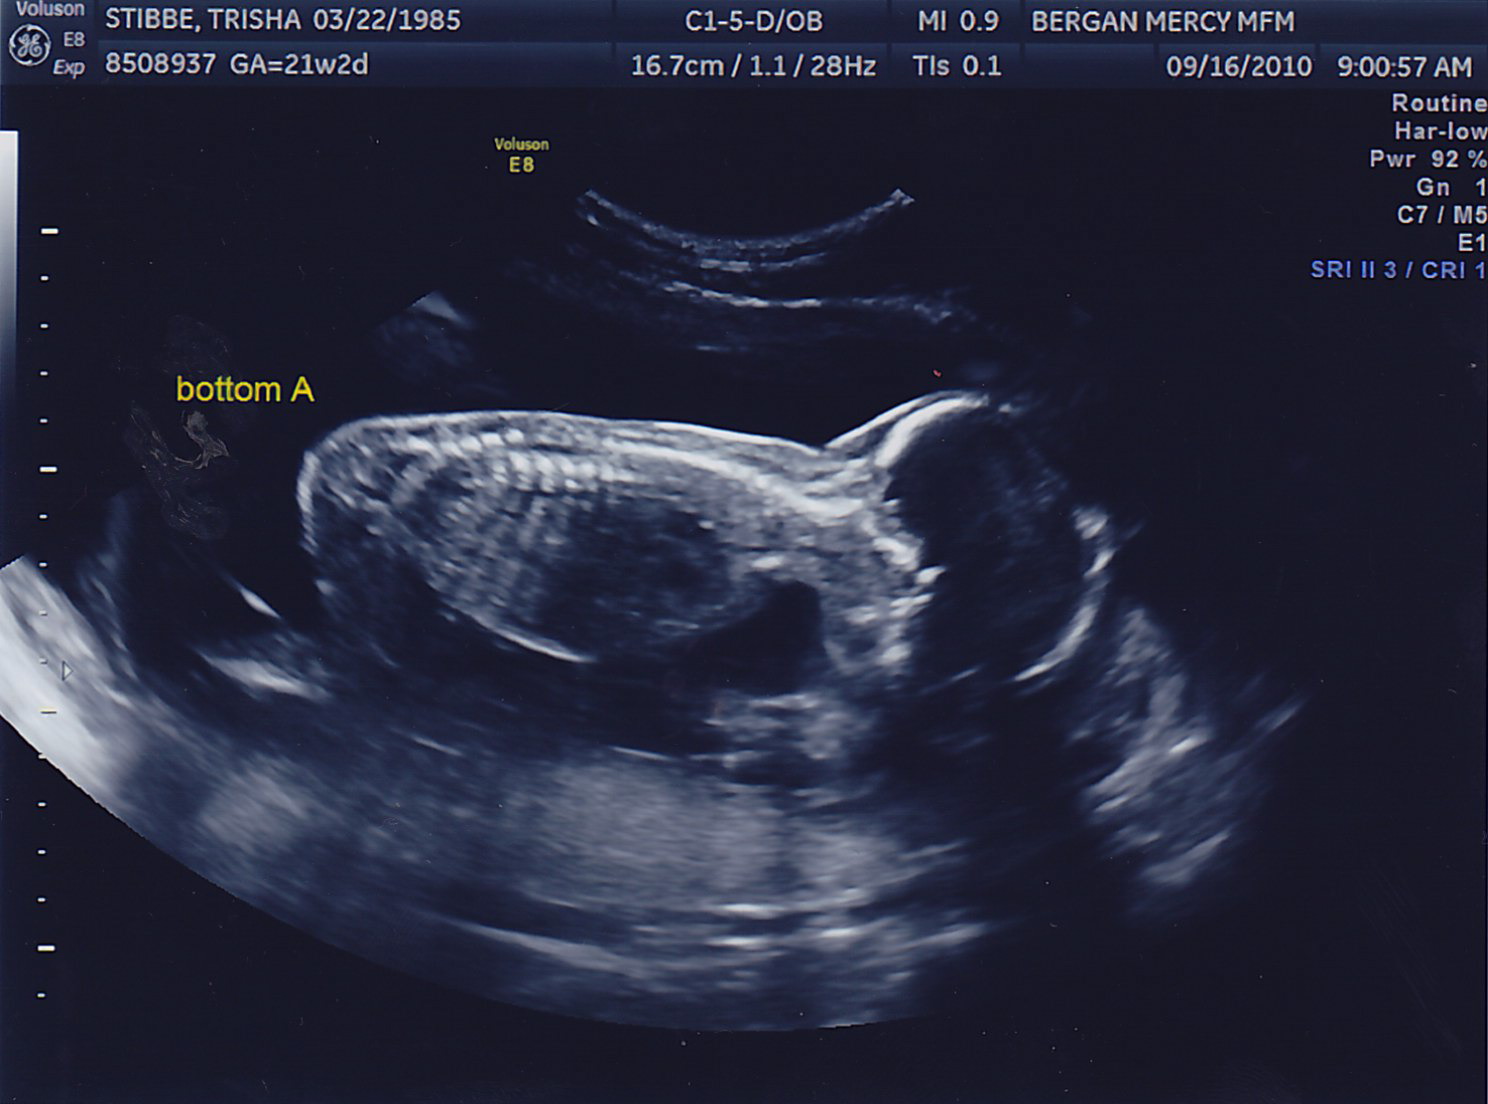

Another successful appointment! Both boys gained weight, we could see the bladder on Baby B (something the doctor needs to keep a close eye on) and the fluid levels in both looked great. No amnio therapy for Mommy today! Here are some more pictures of the little peanuts, who were called “photogenic” by the sonographer today <– very proud Mom-moment 🙂